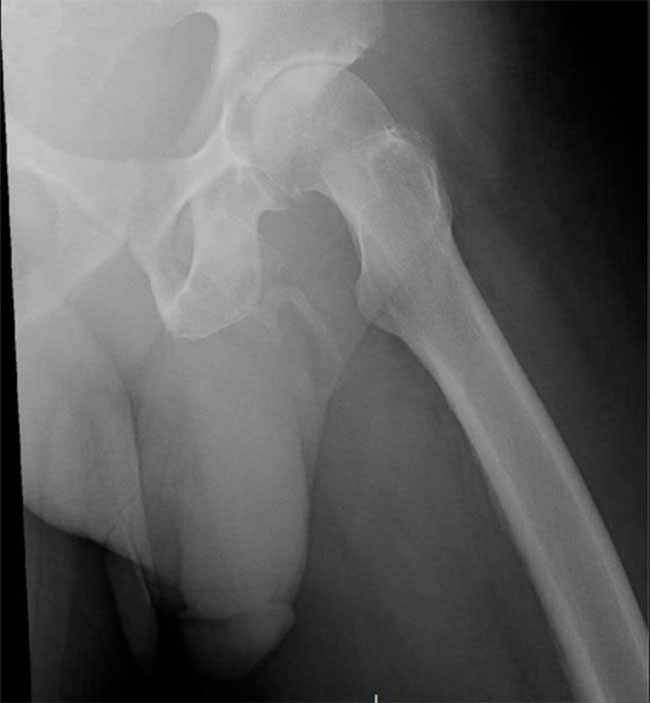

అయితే ఓ వ్యక్తి పురుషాగం ఎముకలా మారుతోంది. ఇది వైద్య చరిత్రలోనే అరుదైన ఘటనగా వైద్యులు అభివర్ణిస్తున్నారు. న్యూయార్క్ కు చెందిన 63 ఏళ్ల వ్యక్తికి ఇటీవల పురుషాంగం వద్ద నొప్పిగా ఉండడంతో బ్రోంక్స్ లోని లింకన్ మెడికల్ - హెల్త్ సెంటర్ లో వైద్య పరీక్షలు చేశారు. అతడి పురుషాంగం వద్ద ఎముక కణాలు ఏర్పడుతున్నట్టు వైద్యులు గుర్తించారు. అయితే వైద్యులు చెప్పినా అతడు పట్టించుకోకుండా వెళ్లిపోయాడు.

తాజాగా ఓ వీధిలో పడిపోయాడు. నడుముకు దెబ్బతగిలింది. నడుస్తున్నప్పుడు మోకాలు బాగా నొప్పి వస్తుందని వైద్యులను ఆశ్రయించగా.. ఎక్స్ రే తీస్తే అతడి పురుషాంగం మరింతగా ఎముకగా మారినట్టు గుర్తించారు. అది పూర్తి ఎముకగా మారబోతోందని హెచ్చరించారు.

పురుషాంగం ఎముకగా మారే ప్రక్రియను అస్థీకరణ (ఓసిఫికేషన్) అంటారని.. అరుదుగా ఏర్పడి ఈ వ్యాధి వల్ల కణజాలాలు పూర్తిగా ఎముకలా మారుతాయని వైద్యులు తెలిపారు. దీనికి సర్జరీ చేయాల్సి ఉంటుందని.. షాక్ వేవ్ థెరపీ ద్వారా ఈ చికిత్స చేస్తామని తెలిపారు. నిర్లక్ష్యం చేస్తే పురుషాగం పూర్తిగా ఎముకగా మారుతుందని వైద్యులు హెచ్చరించారు.